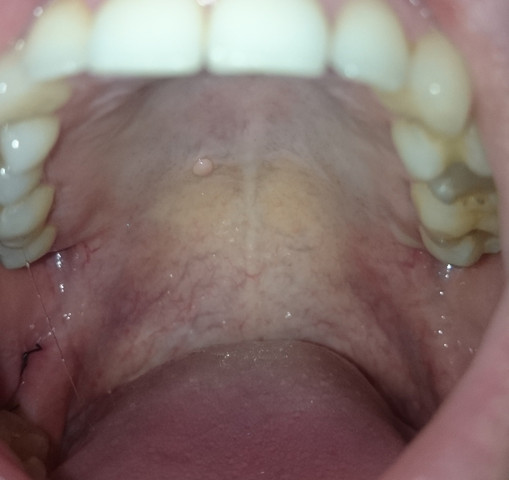

Diese wird genau untersucht. Eine Entzündung am Gaumen fällt meist durch eine schmerzhafte Schwelllung und Rötung auf. Beschwerden am gaumen bei zahnschmerzen hintergrund können zahnschmerzen sein die sich auf den gesamten mund rachen bereich ausdehnen und damit auch den gaumen betreffen können einleitung eine entzündung am gaumen fällt meist durch eine schmerzhafte schwelllung und rötung auf.

Die sorgt dafür dass aus dem Zucker im Honig Wasserstoffperoxid. Zu unterscheiden sind die Entzündung an der Schleimhaut des Gaumens selbst und Entzündungen am Zäpfchen den Mandeln im Gaumensegel.

Hallo ich habe seit ca. Offene stelle am gaumen was tun Gaumenschmerzen. Eine Entzündung am Gaumen fällt meist durch eine schmerzhafte Schwelllung und Rötung auf. Zu diesem Zweck eignen sich Kräuter wie Johanniskraut Kamille Lindenblüten und Nelken die zu einem Tee zubereitet werden. Beim Kauen oder bei Kontakt mit Fruchtsäure. Eine leichte Gaumenreizung kann man schon von zu heißen Nahrungsmitteln bekommen. Aphthen sind eine der häufigsten Krankheiten der Mundschleimhaut.